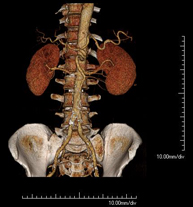

- Angio-TC aorta abdominal  Prueba diagnóstica no invasiva que consiste en el estudio de la arteria aorta abdominal obteniendo imágenes de alta definición anatómica mediante el empleo de un equipo de TC (Tomografía Computarizada) y de contraste yodado. La calidad de las imágenes permite realizar reconstrucciones en 2D y 3D gracias a estaciones de trabajo especializadas en el estudio arterial. Está indicado en aquellos pacientes con enfermedad vascular (aterosclerosis), en aneurismas de aorta, en pacientes con dolor abdominal de posible origen vascular, en estudios pre-quirúrgicos de lesiones adyacentes a la aorta abdominal como "mapa" vascular, etc. La información obtenida de forma no invasiva es indispensable para los pacientes que requieren tratamiento percutáneo o quirúrgico. En aquellos pacientes que solo requieren un seguimiento de las lesiones vasculares, esta técnica es la técnica no invasiva de elección junto con la angio-RM. Prueba diagnóstica no invasiva que consiste en el estudio de la arteria aorta abdominal obteniendo imágenes de alta definición anatómica mediante el empleo de un equipo de TC (Tomografía Computarizada) y de contraste yodado. La calidad de las imágenes permite realizar reconstrucciones en 2D y 3D gracias a estaciones de trabajo especializadas en el estudio arterial. Está indicado en aquellos pacientes con enfermedad vascular (aterosclerosis), en aneurismas de aorta, en pacientes con dolor abdominal de posible origen vascular, en estudios pre-quirúrgicos de lesiones adyacentes a la aorta abdominal como "mapa" vascular, etc. La información obtenida de forma no invasiva es indispensable para los pacientes que requieren tratamiento percutáneo o quirúrgico. En aquellos pacientes que solo requieren un seguimiento de las lesiones vasculares, esta técnica es la técnica no invasiva de elección junto con la angio-RM.

- Angio-TC arterias renales  Prueba diagnóstica no invasiva que consiste en el estudio de las arterias renales obteniendo imágenes de alta definición anatómica mediante el empleo de un equipo de TC (Tomografía Computarizada) y de contraste yodado. La calidad de las imágenes permite realizar reconstrucciones en 2D y 3D gracias a estaciones de trabajo especializadas en el estudio arterial. Esta prueba está indicada, por ejemplo, en aquellos pacientes que sufren de HTA refractaria al tratamiento, en pacientes con lesiones renales para tener un mapa "vascular" pre-quirúrgico, etc. Prueba diagnóstica no invasiva que consiste en el estudio de las arterias renales obteniendo imágenes de alta definición anatómica mediante el empleo de un equipo de TC (Tomografía Computarizada) y de contraste yodado. La calidad de las imágenes permite realizar reconstrucciones en 2D y 3D gracias a estaciones de trabajo especializadas en el estudio arterial. Esta prueba está indicada, por ejemplo, en aquellos pacientes que sufren de HTA refractaria al tratamiento, en pacientes con lesiones renales para tener un mapa "vascular" pre-quirúrgico, etc.

- Angio-TC aorto-ilíaco Prueba diagnóstica no invasiva que consiste en el estudio de las arterias ilíacas y la aorta abdominal obteniendo imágenes de alta definición anatómica mediante el empleo de un equipo de TC (Tomografía Computarizada) y de contraste yodado. La calidad de las imágenes permite realizar reconstrucciones en 2D y 3D gracias a estaciones de trabajo especializadas en el estudio arterial. Esta prueba está especialmente indicada como estudio pre-quirúrgico (mapa vascular) antes de intervenciones percutáneas o quirúrgicas de aorta abdominal, como el estudio complementario en pacientes con isquemia de miembros inferiores, etc. Prueba diagnóstica no invasiva que consiste en el estudio de las arterias ilíacas y la aorta abdominal obteniendo imágenes de alta definición anatómica mediante el empleo de un equipo de TC (Tomografía Computarizada) y de contraste yodado. La calidad de las imágenes permite realizar reconstrucciones en 2D y 3D gracias a estaciones de trabajo especializadas en el estudio arterial. Esta prueba está especialmente indicada como estudio pre-quirúrgico (mapa vascular) antes de intervenciones percutáneas o quirúrgicas de aorta abdominal, como el estudio complementario en pacientes con isquemia de miembros inferiores, etc.